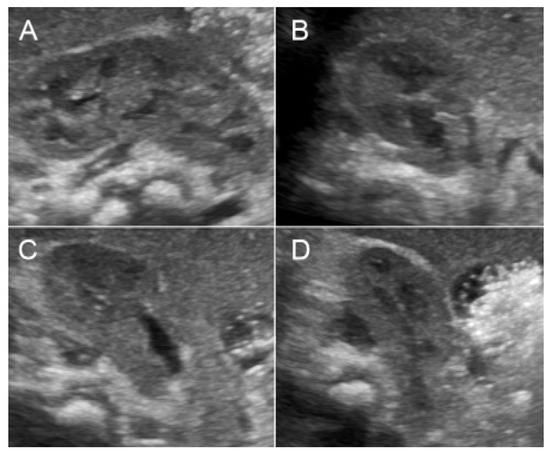

Figure 2. Malrotation of the right kidney with abnormally lateral-posterior renal pelvis (A) sagittal scan; (BD) cross-sectional scan at upper, mid and lower portion).

A 32-year-old pregnant woman, G4 P2102, attended her first visit of antenatal care at 23+3 weeks of gestation. Ultrasound examination for anomaly screening demonstrated cardiac defects, including double-outlet right ventricle: DORV-TOF type, with severe pulmonary stenosis (Figure 1) and left superior vena cava. Detailed ultrasound showed no associated abnormalities. Fetal biometry was consistent with gestational age except abdominal circumference and estimated fetal weight, which were relatively low (at 10th percentile), reflecting some degree of growth restriction. However, detailed ultrasound on the follow-up scans at 28 weeks of gestation showed subtle abnormalities, including malrotation of both kidneys, the hilum or renal pelvis facing posteriorly to the abdominal wall (Figure 2). Furthermore, 3D-ultrasound revealed abnormal external ear structure (markedly prominent crus of anti-helix) (Figure 3). Non-stress tests (NST) showed spontaneous fetal heart rate (FHR) accelerations (normal reactive tests) (23+3 weeks). Interestingly, the fetus showed persistent non-response to acoustic stimulation tests at 26, 30, 32, 36 and 38 weeks (no FHR accelerations as well as no quickening perceived by ultrasound) (Figure 4), probably reflective of auditory dysfunction. Based on the findings of heart defect, ear defect, renal defect and growth restriction, several differential diagnoses were listed, including CHARGE syndrome. Theoretically, fetal blood sampling for molecular genetic tests should be performed. Nevertheless, since no lethal condition was identified and the couple wanted to continue pregnancy regardless of investigation results, prenatal invasive diagnosis was avoided, and we waited for postnatal work-up instead. She had no significant underlying disease and no familial history of hereditary diseases. Her pregnancy was uneventful except that she developed gestational diabetes (GDM) at 28 weeks of gestation, which was well-controlled with diabetic diet.